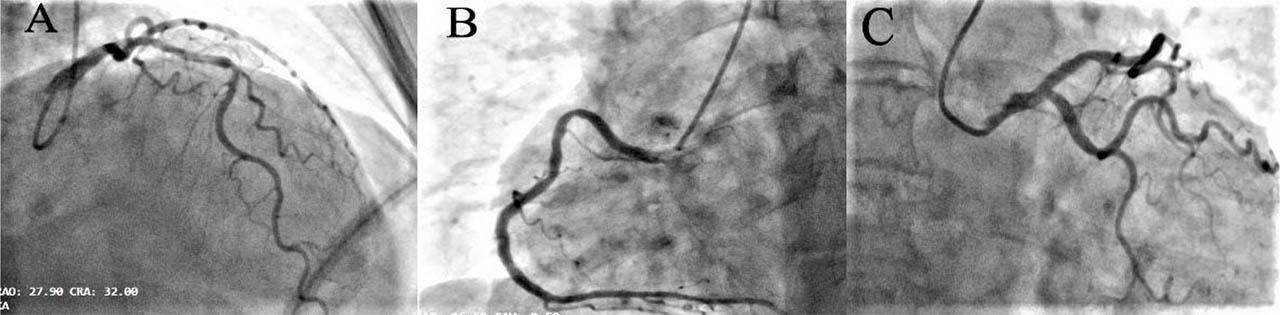

Figure 2

Coronary angiography. Panel A: The left anterior descending artery (LAD) showing permeable proximal stent and no other significant stenosis; Panel B: Right coronary artery (RCA) with proximal plaque with no angiographic significance; Panel C: Left circumflex artery (LCX) with no lesions.